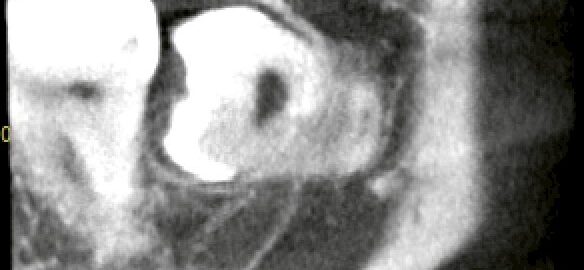

神経に近い下顎の深い埋伏智歯でも抜歯すべき?CTでわかった嚢胞リスクと判断基準

こんにちは。東京都中央区銀座5丁目にある 【親知らず・顎関節症クリニック銀座(通称:オヤアゴクリニック)】です。 当院は以下の3つに特化した歯科クリニックです。 * 親知らずの抜歯 * 顎関節症の治療 * アスリートのた … 続きを読む 神経に近い下顎の深い埋伏智歯でも抜歯すべき?CTでわかった嚢胞リスクと判断基準